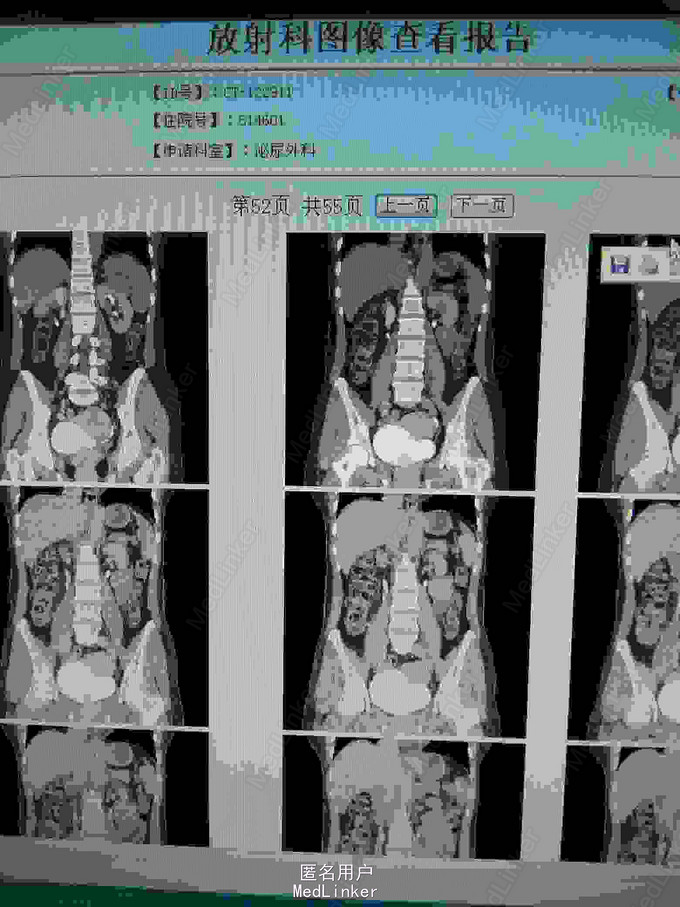

ct提示右侧双肾输尿管畸形,输尿管囊肿。总肾功能正常,尿常规正常,未发现结石等异常,右上位肾脏及输尿管扩张。